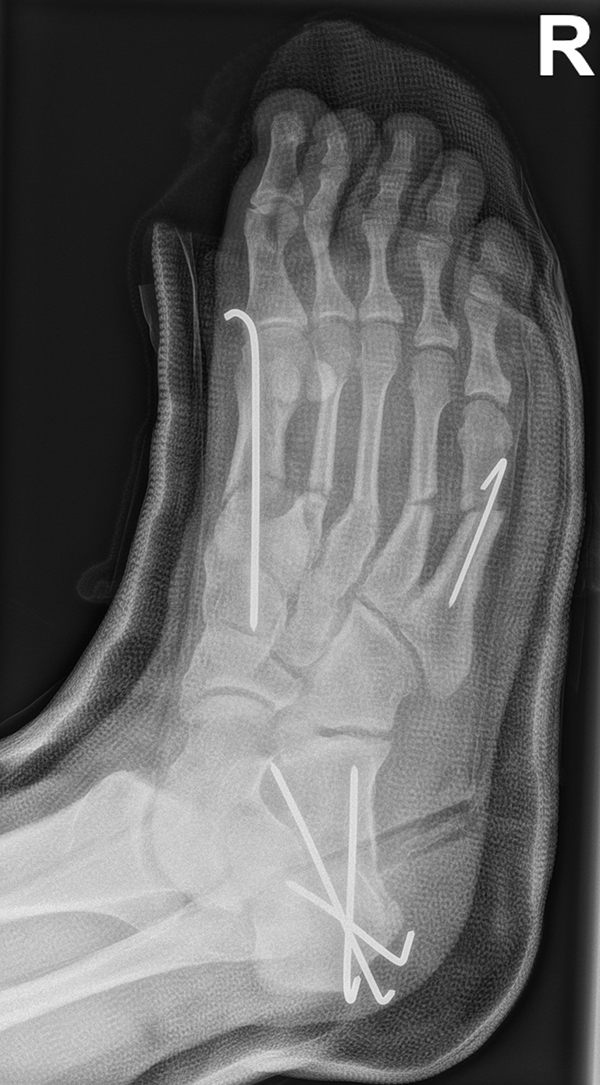

Welche minimalinvasiven fußchirurgischen Techniken in der Versorgung von Kinder- und Jugendfüßen geeignet und welche Indikationen sinnvoll sind, ist im Vergleich zu ausgewachsenen Füßen leicht abweichend. Hauptursache hierfür sind die Wachstumsfugen (Abb. 1).

Abb.1 a-b: Beispiel einer noch offenen Wachstumsfuge im dorsalen Bereich des Calcaneus: (a) Alter 6 und (b) Alter 9 Jahre.

In der Regel bestehen aktive Wachstumsfugen bei Mädchen bis zum 12. und bei Jungen bis zum 14. Lebensjahr, mit Abweichungen von einem Jahr nach unten und nach oben. Präzise Informationen unter anderem darüber gibt das präoperative Röntgenbild (Abb. 2).

Abb. 2 a-c: offene Wachstumsfugen MT I Basis und Zehen (a), teilweise geöffnete Wachstumsfugen (b) und geschlossene Wachstumsfugen (c).